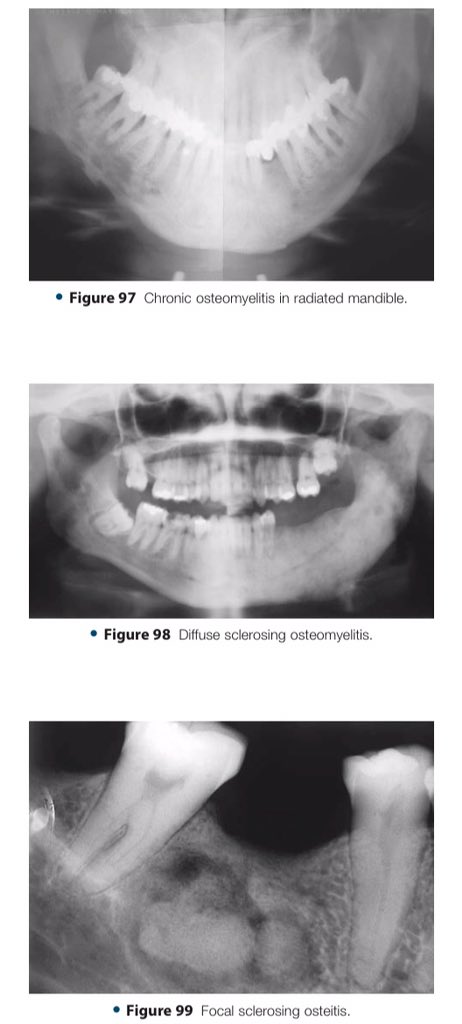

🔍| Differential Diagnosis Approach to Jaw Lesions. #aboutDent